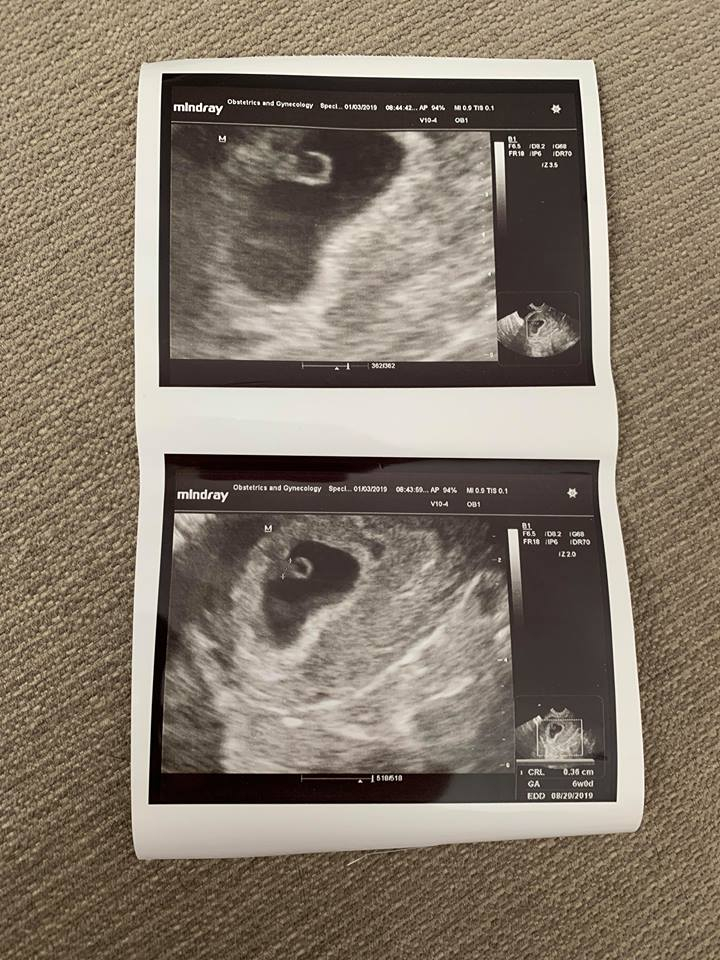

Had our first appointment today. Baby is measuring a few days behind but nothing too worrisome there. Saw the heartbeat although the doc didn’t give us an exact heart rate. He did see a blood clot or subchorionic hematoma that increases risk of MC. So now I have that to worry about. We will go back in 2 weeks to see if the blood clot is reabsorbing. So it overall it went okay, but not great.

Had our first confirmation US yesterday morning. We were guestimating closer to seven weeks, but babe measured at 6w0d. We couldn't hear the heartbeat, but we could see flutters. We go back in three weeks for another US to confirm everything is progressing normally.